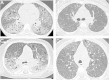

Methods: Data were retrospectively collected from medical files. Radiological and pathological elements were reviewed by two pediatric radiologists and three pathologists, respectively.

Results: Thirteen cases were familial and 32/34 (94%) cases were family connected. Disease onset occurred in the first six months of life in 82% of the patients. Thoracic computed tomography scans showed the typical "crazy-paving" pattern in 94% of cases. Respiratory disease was associated with a liver disorder, with the detection of liver enlargement at diagnosis in 56% of cases. The course of the disease was characterized by frequent progression to chronic respiratory insufficiency, accompanied by the appearance of cholesterol granulomas and pulmonary fibrosis. Overall prognosis was poor, with a mortality of 59% and an overall five-year survival rate from birth of 64%. Whole-lung lavages were performed in 21 patients, with no significant effect on survival. Liver disease progressed to cirrhosis in 18% of children, with no severe complication.